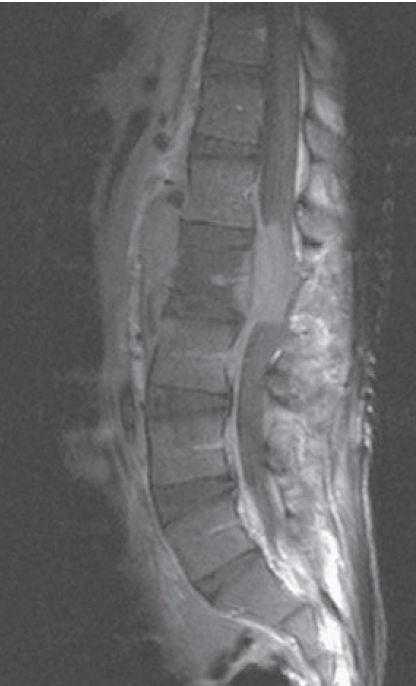

Een 14-jarige Ghanese jongen met een blanco voorgeschiedenis had laag lumbale, niet uitstralende rugpijn die sinds 4 maanden bestond. Sinds 1 maand vertoonde hij progressieve motorische en sensibele uitvalsverschijnselen in de benen (caudasyndroom), waarna lopen niet meer mogelijk was. In 3 maanden tijd verloor hij tevens 10 kg aan lichaamsgewicht.